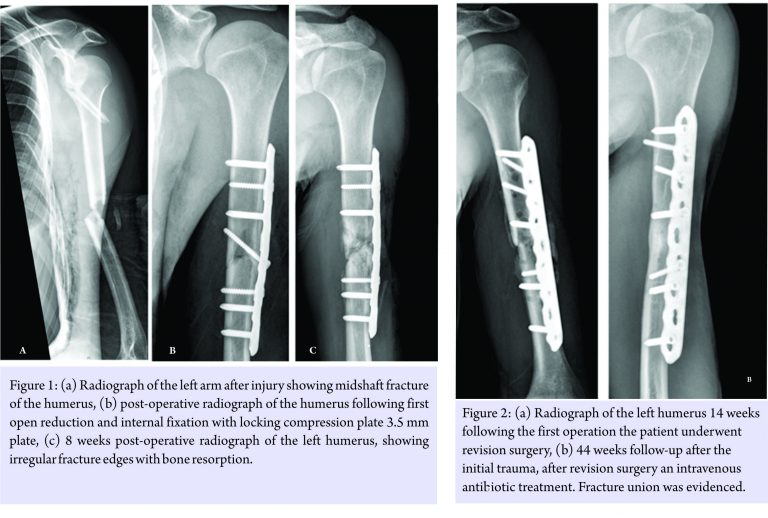

A 28-year-old, previously healthy archeological student was involved in a motor vehicle accident as a motorcyclist who slipped on an oil spill on an urban road. He was admitted to the trauma unit in our hospital. Urgent whole body computed tomographic scan revealed multiple injuries including a left lung contusion, hemothorax, fractures of the fourth to tenth left ribs, left scapular fracture and a left mid-shaft, and transverse humeral shaft fracture (Fig. 1a). The chest was decompressed in the emergency department with a chest drain; the humeral shaft was initially immobilized using a sugar tongue splint. The patient reported a medical history of smoking 10 cigarettes per day.

Due to the fact that the patient had multiple injuries and the suboptimal alignment of his fracture, and after discussing with the patients the options of operative versus non-operative treatment, including faster rehabilitation, both the patient and the senior author decided to treat the humerus fracture operatively. At the 11th-day post-injury, the patient was taken to the operating room for open reduction and internal fixation (ORIF) of the left humeral fracture. An anterolateral approach was carried out. After incision of the brachialis muscle, a high amount of liquid pus poured out of the fracture site. Following culturing, meticulous, and extensive debridement of the fracture site and surrounding soft tissue was carried out; At this point – a decision was made to go on with the fixation of the fracture, to provide stability, necessary also to resist infection [8,9,10], taking the calculated risk of ongoing infection. Fixation was, therefore, done using a 4.5 mm locking plate (locking compression plate, Synthes, Solothurn, Switzerland) with a lag screw (Fig. 1b). Intravenous treatment with cefazoline 1 g was initiated and continued for 6 weeks. Intraoperative cultures were positive for methicillin-sensitive Staphylococcus aureus. At that point, blood cultures obtained during the single spike of fever had yielded the same organism. Following antibiotic treatment CRP value dropped from 2.6 mmol/l preoperatively to 1.77 mmol/l 9 days postoperatively. 8 weeks postoperatively the patient returned to the emergency room with a purulent discharge from his incision. An ultrasound of the surgical scar revealed a small 3*2.5*0.6 cm collection of fluid which was drained. With suspected ongoing infection, coupled with implant loosening (Fig. 1c) the patient was taken to the operating room for two consecutive debridements of gross infection with the insertion of gentamycin impregnated cement beads, which were later removed. 14 weeks after the index procedure, an antibiotic window was undertaken for 10 days, after which the patient was taken back to the operating room for repeat surgery, contemplating the removal of hardware as an interim measure followed by second stage ORIF. However, since the operative field did not show gross signs of infection, and most of the bone was viable, it was decided to go on with debridement of the bone ends and repeat ORIF using a longer plate in the mode of compression (Fig. 2a). Intraoperative cultures obtained during this procedure were still positive for the same microorganism. Therefore, antimicrobial treatment with intravenous cefazolin followed by oral suppressive antibiotics consisting of cloxacillin and rifampicin was administered for 3 months. On 44 weeks follow-up after the initial trauma; solid fracture union was evident both clinically and radiographically (Fig. 2b) with cessation of pain and full elbow and shoulder range of motion (Fig. 3) with no sign of infection.